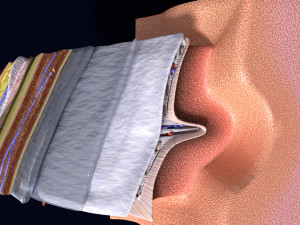

Brain with meninges scalp detailed labelled 3D 3D मॉडल

A blend model of brain along with its covering layers (meninges), skull bone and scalp labelled in detail and anatomically precise. The parts depicted are white, gray, pia, arachnoid, dura, bone, skin, fat, aponeurosis, periosteum, falx cerebri and more.

The material is high resolution image textures and normal maps based on non overlapping UVs. The texture and normal maps are packed with the blend file itself.